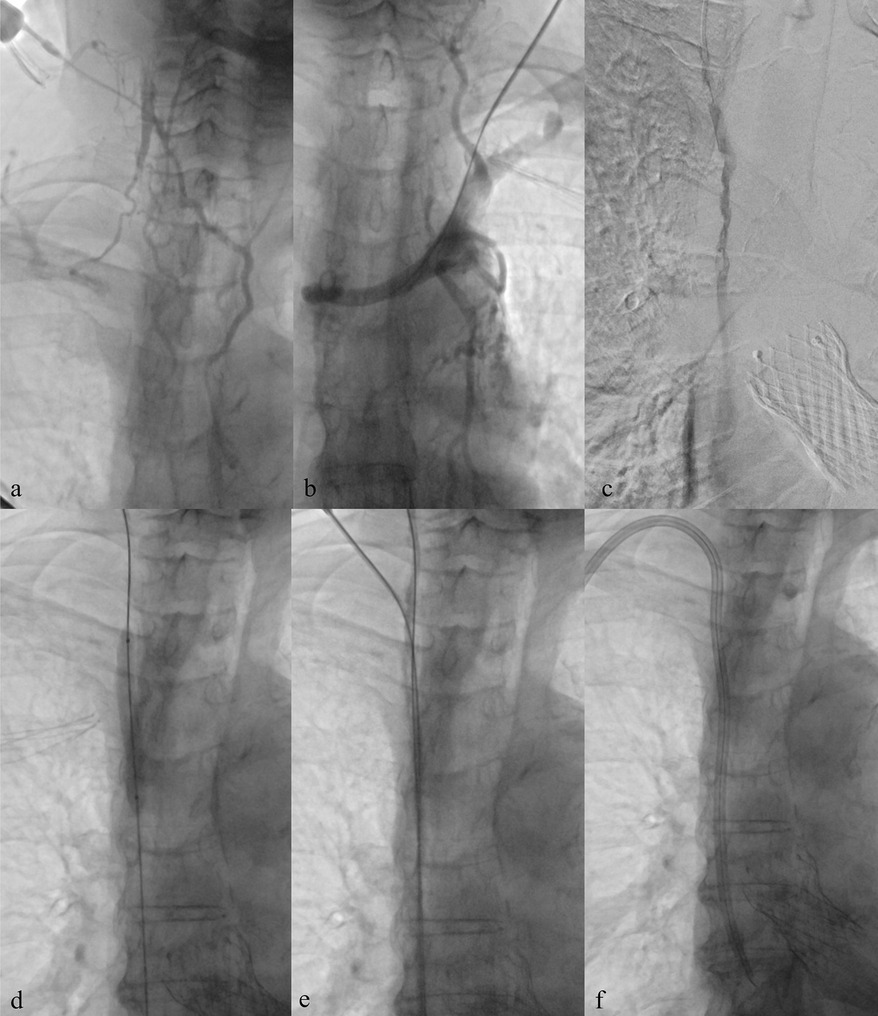

Background: Tunneled cuffed catheter (TCC) remains a crucial vascular access option for patients undergoing hemodialysis, particularly in those who are not candidates for arteriovenous fistulas or grafts. However, placement carries immediate and delayed complications. Objective: This narrative review aims to provide a comprehensive overview of the complications encountered during and after the placement of a TCC for hemodialysis, highlighting current evidence, risk factors, prevention strategies, and management approaches. Methods: A critical selection of relevant literature was performed through PubMed and Scopus databases, focusing on articles published in the last two decades. Particular attention was given to studies reporting on mechanical, infectious, thrombotic, and late-onset complications, as well as technical factors influencing outcomes. Results: Complications of TCCs can be classified as immediate (e.g., arterial puncture, pneumothorax, bleeding), early (e.g., catheter malposition, exit-site infections), and late (e.g., central venous stenosis, catheter-related bloodstream infections, thrombosis). Patient-and procedure-related factors increase risk. Ultrasound and fluoroscopy, strict sterility, and timely management reduce complications rates. Conclusion: TCCs are indispensable in selected patients, but understanding their complications is key to patient safety and outcomes. Optimal outcomes depend on accurate patient selection, operator expertise, and standardized post-placement care.